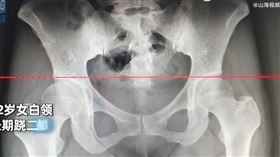

翹腳釀3症狀!不只脊椎歪 醫:暫時性麻痺

不少人有翹腳的習慣,雖然很舒服,卻會危害健康。胸腔暨...

翹二郎腿有害身體 醫師:影響房事

許多人坐著,會忍不住翹起「二郎腿」,但這個動作其實傷...

別翹二郎腿!壓迫4部位恐椎間盤痛、頻尿

你有翹二郎腿的習慣嗎?骨科醫師嚴可倫表示,相信許多人...